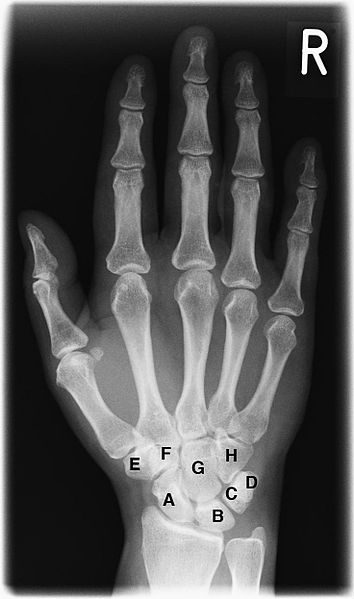

Plain radiograph of a human hand showing the carpal, metacarpal, and phalangeal bones.